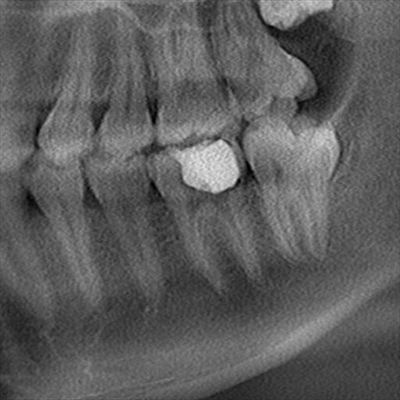

初診時の状態です。

左下第一大臼歯がむし歯によって昨日抜髄されています。

102017.01.27.jpg

根管充填後のレントゲン写真です。